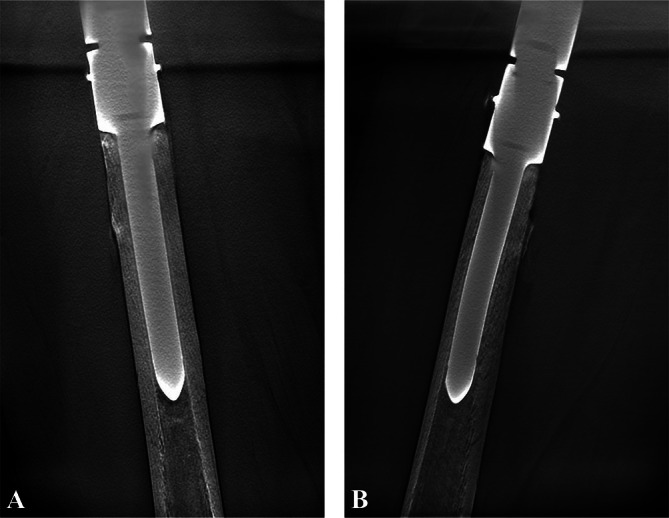

Methods: We retrospectively reviewed 76 patients (49 males, 27 females; mean age 41 years, range 14-78 years) who underwent proximal femoral replacement with a modular uncemented endoprosthesis between 2015 and 2022. The mean follow-up was 63.4 months (median: 60.5 months; range: 12-104 months). Functional outcomes were assessed using the Musculoskeletal Tumor Society (MSTS) score, while complications were classified based on the Henderson et al. system. Survivorship analyses were conducted using Kaplan-Meier methods.